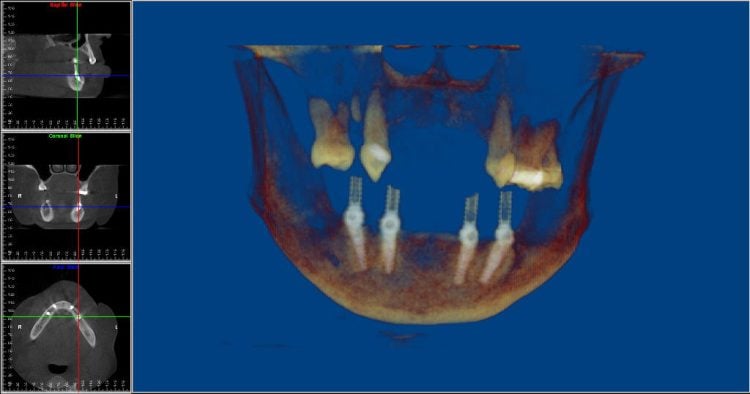

The process starts when a CAT scan is taken of the patient’s jawbone. This CAT scan allows for the generation of a three-dimensional model of the jawbone that can then be used in virtual reality software to plan the implant placement without the presence of the patient. The results are more accurate implant placement, and less chair time for the patient at the surgery office.

Multiple failing restorations and periodontal disease

Immediately following surgery with screw retained temporary prosthesis in place. Patient went home with stable teeth.

This patient had periodontal disease and multiple failing crowns.

Immediately following surgery with screw retained temporary prosthesis in place. Patient went home with stable teeth.